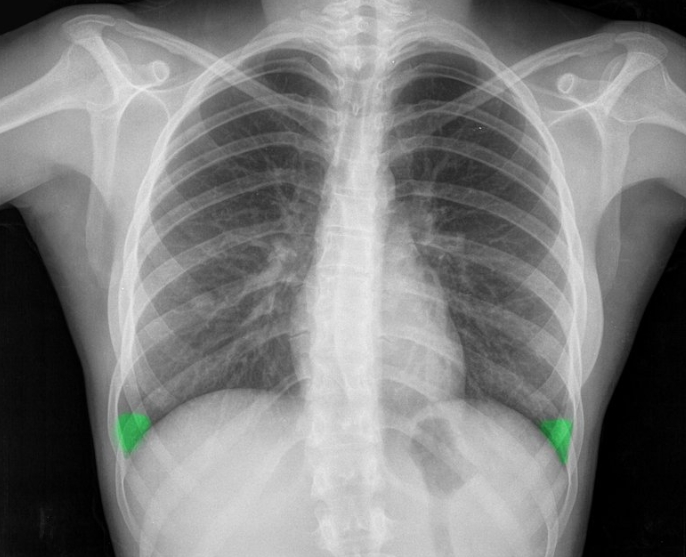

X-ray 사진 보는 법

X-ray 사진은 기본 원리를 알면 꽤 흥미로워요. 뼈처럼 단단한 조직은 방사선을 거의 통과하지 않아 흰색으로 보이고, 근육이나 지방 같은 조직은 회색, 공기처럼 비어 있는 공간은 검정색으로 나옵니다. 그래서 폐는 검게, 갈비뼈는 하얗게 보이는 거죠. 물론 정밀한 판독은 전문가에게 맡겨야 하지만, 기본적인 구조만 알아도 진료를 이해하는 데 큰 도움이 돼요.